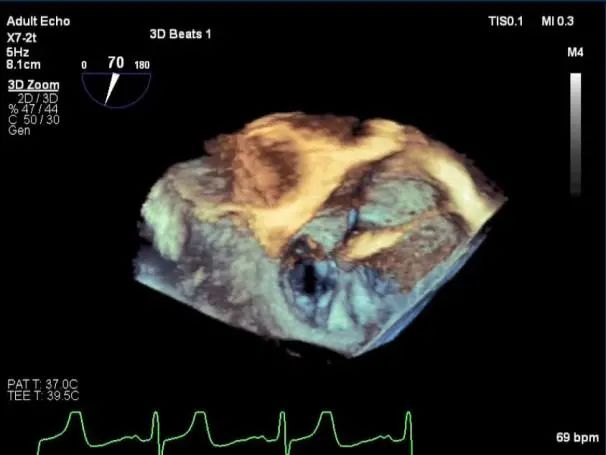

三维超声心动图显示第一枚XTR夹子释放,残余返流主要位于外侧

三维超声心动图显示第二枚XTR夹子释放